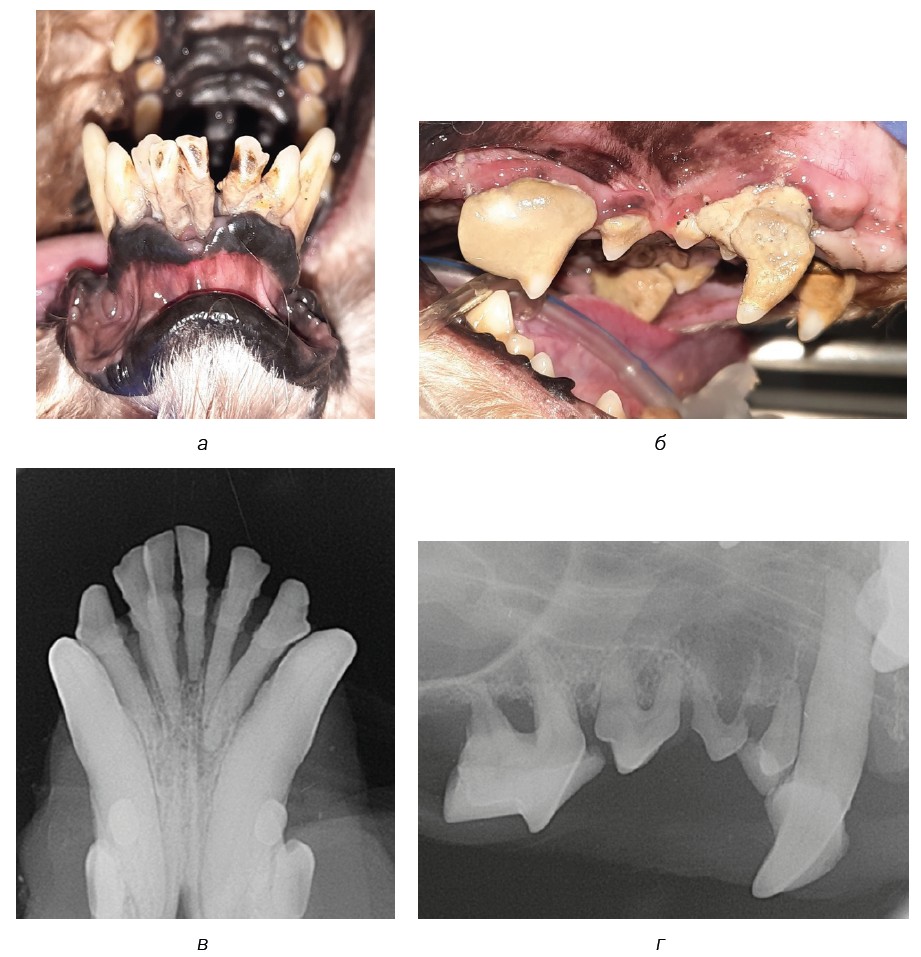

Fig. 6. Dental calculus: a — stage 1 (409 tooth) and stage 3 (404 tooth); б — stage 2 (409–405 teeth); в and г — intraoral radiograph for stage 2 dental calculus.

Source: VTC "Dentalvet".